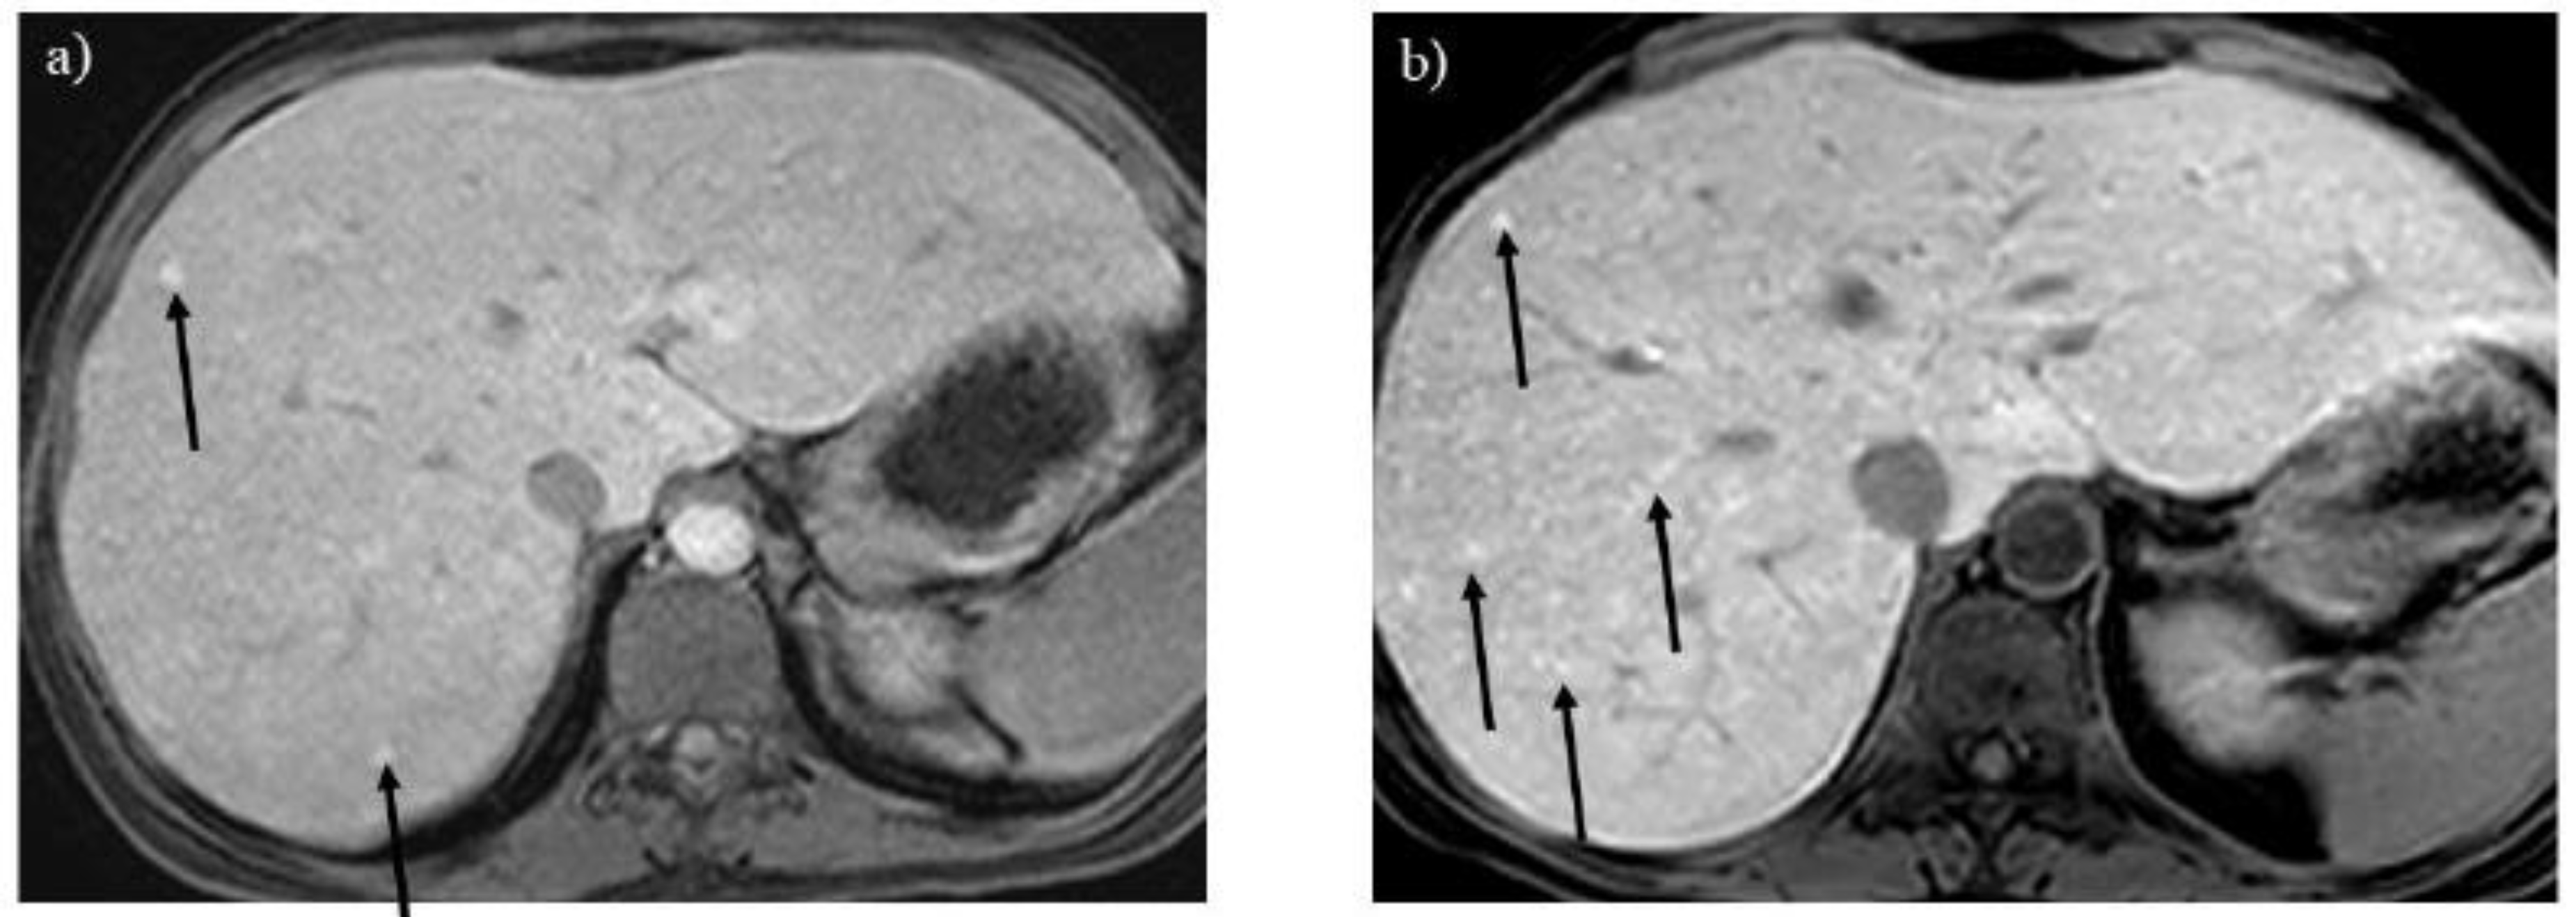

Figure 6. A 16-year-old boy with glycogen storage disease type Ib. Opposed-phase T1-weighted imaging (A) reveals hepatosplenomegaly with a signal drop in the liver, suggesting hepatic steatosis. After 7 years, the liver signal normalizes, whereas the spinal erector and intercostal muscles do not grow fully (B, arrows). .

Hepatic steatosis is often associated with GSDs because of malnutrition and lipid metabolism disorders [3,6]. Dual-echo T1-weighted imaging reveals hepatic steatosis (Figures 6A and 7A) [9]. It is also useful for monitoring the severity of hepatic steatosis. The liver signal normalizes on opposed-phase T1-weighted imaging in patients with GSD type I following successful dietary therapies (Figure 6B).

Glycogen is consumed in skeletal muscles during physical activity. Growth retardation, atrophy, and clinical symptoms, including muscular weakness and cramping, are observed in children and young adults with GSDs [1,2]. MRI may be useful for evaluating the volume and fatty infiltration in skeletal muscles (Figure 6B). Because MRI can visualize the distribution of involved muscles in a wide range of view, it may be useful for distinguishing GSDs from muscular dystrophies and neuromuscular disorders [19].